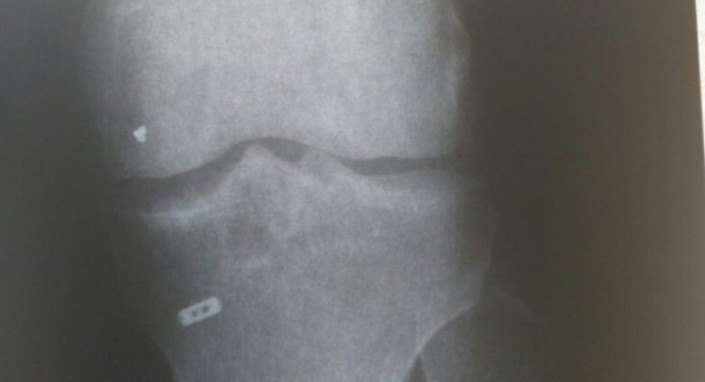

В марте 2016 года преподавателя казахстанского вуза Ерлана Тайкулакова прооперировали в новосибирской клинике. К российским врачам 34-летний геофизик обратился с проблемой со связками в коленном суставе.

Как рассказывает адвокат Ерлана Тайкулакова Нариман Закирьянов, после операции молодого ученого продолжали беспокоить боли в колене. С болями в колене мужчина ходил целый год.

"У него боли не прекращались, даже судороги были. Он думал, что это постреабилитационный период, что это естественное явление, что нога, наверное, заживает. Спустя год он сделал МРТ, которое показало, что в колене есть инородный предмет. Мы сразу обратились в клинику за разъяснениями, они сказали, что, возможно, это часть металлического инструмента", - рассказал адвокат Нариман Закирьянов.

По словам адвоката, Ерлан Тайкулаков до сих продолжает ходить с инородным телом в колене. Сейчас он планирует обратиться за помощью к зарубежным врачам.

"Эта железка до сих пор в ноге. Операция дорогостоящая, она стоит за рубежом порядка 10 тысяч долларов. У него средств не было, соответственно, мы требовали эту сумму с клиники. Он не требует деньги в корыстных целях, мы требовали деньги на операцию, чтобы этот предмет удалить", - отметил адвокат.